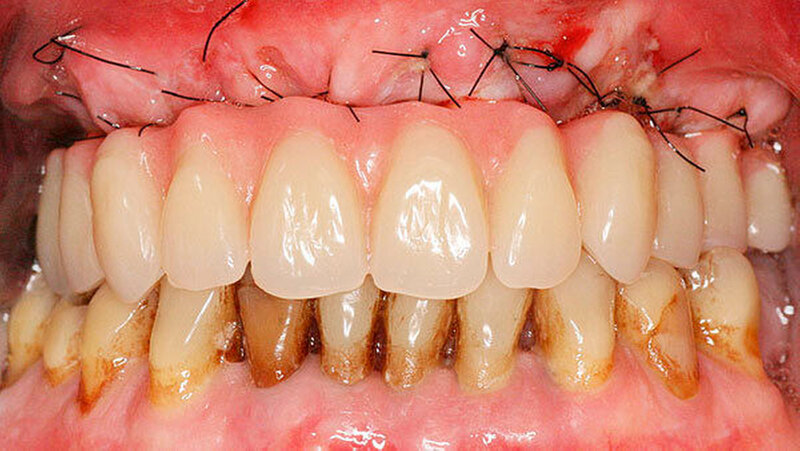

Entscheidend für den Erfolg dieses Konzepts ist die Hygienefähigkeit des Zahnersatzes. Die Basis des Zahnersatzes sollte konvex gestaltet werden und nur linear zum Kieferkamm Kontakt haben (Abbildung 1d). Diese Gestaltung erleichtert eine einfache Mundhygiene mit Interdentalbürsten und Zahnseide. Die Hygienefähigkeit einer All-on-4 Konstruktion ist somit vergleichbar mit einer Stegversorgung. Entscheidend für die Ästhetik ist die präoperative Feststellung der Lippenlachlinie. Diese entscheidet über die Resektionshöhe des Kieferkamms. Die Ästhetik wird bei dieser Versorgungsart ausschließlich über den Zahnersatz erreicht (Abbildung 1d). Die „rote Ästhetik“ kann durch die Verwendung von Prothesenkunststoff individuell und natürlich gestaltet werden. Der Zahnersatz ist bei diesem Konzept okklusal mit den Implantaten verschraubt (Abbildung 1c). Bei Notwendigkeit, zum Beispiel bei Reparaturen, kann dieser durch den Behandelnden leicht ab- genommen werden.

Eine erhebliche Erweiterung der Indikation des All-on-4 Konzeptes konnte durch den Einsatz von Zygoma-Implantaten erzielt werden. Zygoma-Implantate werden im Os zygomaticum verankert und erreichen auch in Situationen mit starker Kieferkammatrophie eine hohe Primärstabilität. Herkömmliche augmentative Verfahren können so vermieden werden. Zygoma-Implantate wurden zunächst bei Patienten mit besonderen Dysplasien im Kieferbereich und bei Tumorpatienten nach Resektion von Kieferanteilen eingesetzt. Balshi war einer der ersten Kliniker, der mit speziell gestalteten Implantaten entsprechende Fälle versorgte. Die Übertragung des All-on-4 Konzeptes auf Zygoma-Implantat-getragene Versorgungen ist insbesondere mit dem Namen Malavez verbunden, die sich sehr um diese Technik verdient gemacht hat. Dieses Konzept auf Zygoma-Implantaten wird angewendet in Fällen mit ausgeprägter Kieferkammatrophie im Oberkiefer (Abbildung 4a). Die Zygoma-Implantate werden in aller Regel in ITN inseriert. Lediglich ein externer Sinuslift ist als augmentative Maßnahme notwendig (Abbildungen 4b und c). Durch dieses Vorgehen können aufwändige augmentative Verfahren umgangen werden. Die prothetische Versorgung der Zygoma-Implantate entspricht dem Vorgehen wie beim All-on-4 Konzept und erfolgt einen Tag postoperativ. Erreicht wird, wie beim ursprünglichen All-on-4 Konzept, eine festsitzende Sofortversorgung (Abbildungen 3 und 4d).